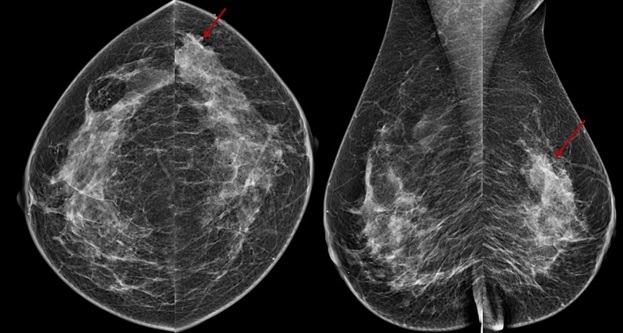

عکس ماموگرافی زنان

بعد از انجام ماموگرافی عکس ماموگرافی یا سی دی آن به شما تحویل داده می شود. عکس ماموگرافی بر اساس نوع دستگاه ماموگرافی و نمای تصویر برداری ظاهر متفاوتی دارد. نماهای مختلف ماموگرافی به تشخیص دقیق تر ضایعه کمک می کند. در ادامه چند نوع عکس ماموگرافی را مشاهده می کنید.